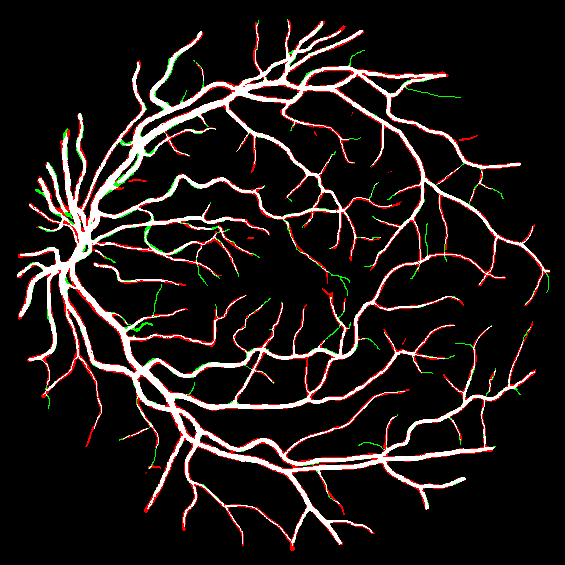

Fig. 2: An example from the DRIVE dataset. Stratification (first row, left to right): (1) input image, (2) raw mask, (3) stem mask, (4) thin mask; Segmentation Results (second row): (5) overall prediction (red are false positive area while green are false negative area), (6) raw prediction, (7) stem prediction, (8) thin prediction (of the Ngsubscript𝑁𝑔N_{g} stream)

To justify the performance of our model, we compare the 4 metrics with 8 representative previous works from all 3 open-access datasets. The comparison results presented in Table 1 show that our MP-Net model outperforms the state-of-the-art methods regarding accuracy and AUC𝐴𝑈𝐶AUC in all three datasets, which meter the practical prediction quality and the overall prediction quality independent on thresholding specifications. The AUC𝐴𝑈𝐶AUC advancement is greater in the DRIVE dataset. It’s related to the fact that the DRIVE dataset contains more thin vessels, which is the main target of our model. Specificity is also the highest in DRIVE and CHASE_DB1 while sensitivity is highest in STARE. Particularly, our method outperforms ML-UNet [2] and JL-UNet [4] which adopt a different multi-class approach to also especially tackle the thin-vessels challenge. Figure 2 shows an example of our segmentation maps on DRIVE. As can be seen, most thin vessels and boundary areas have been meticulously picked up.